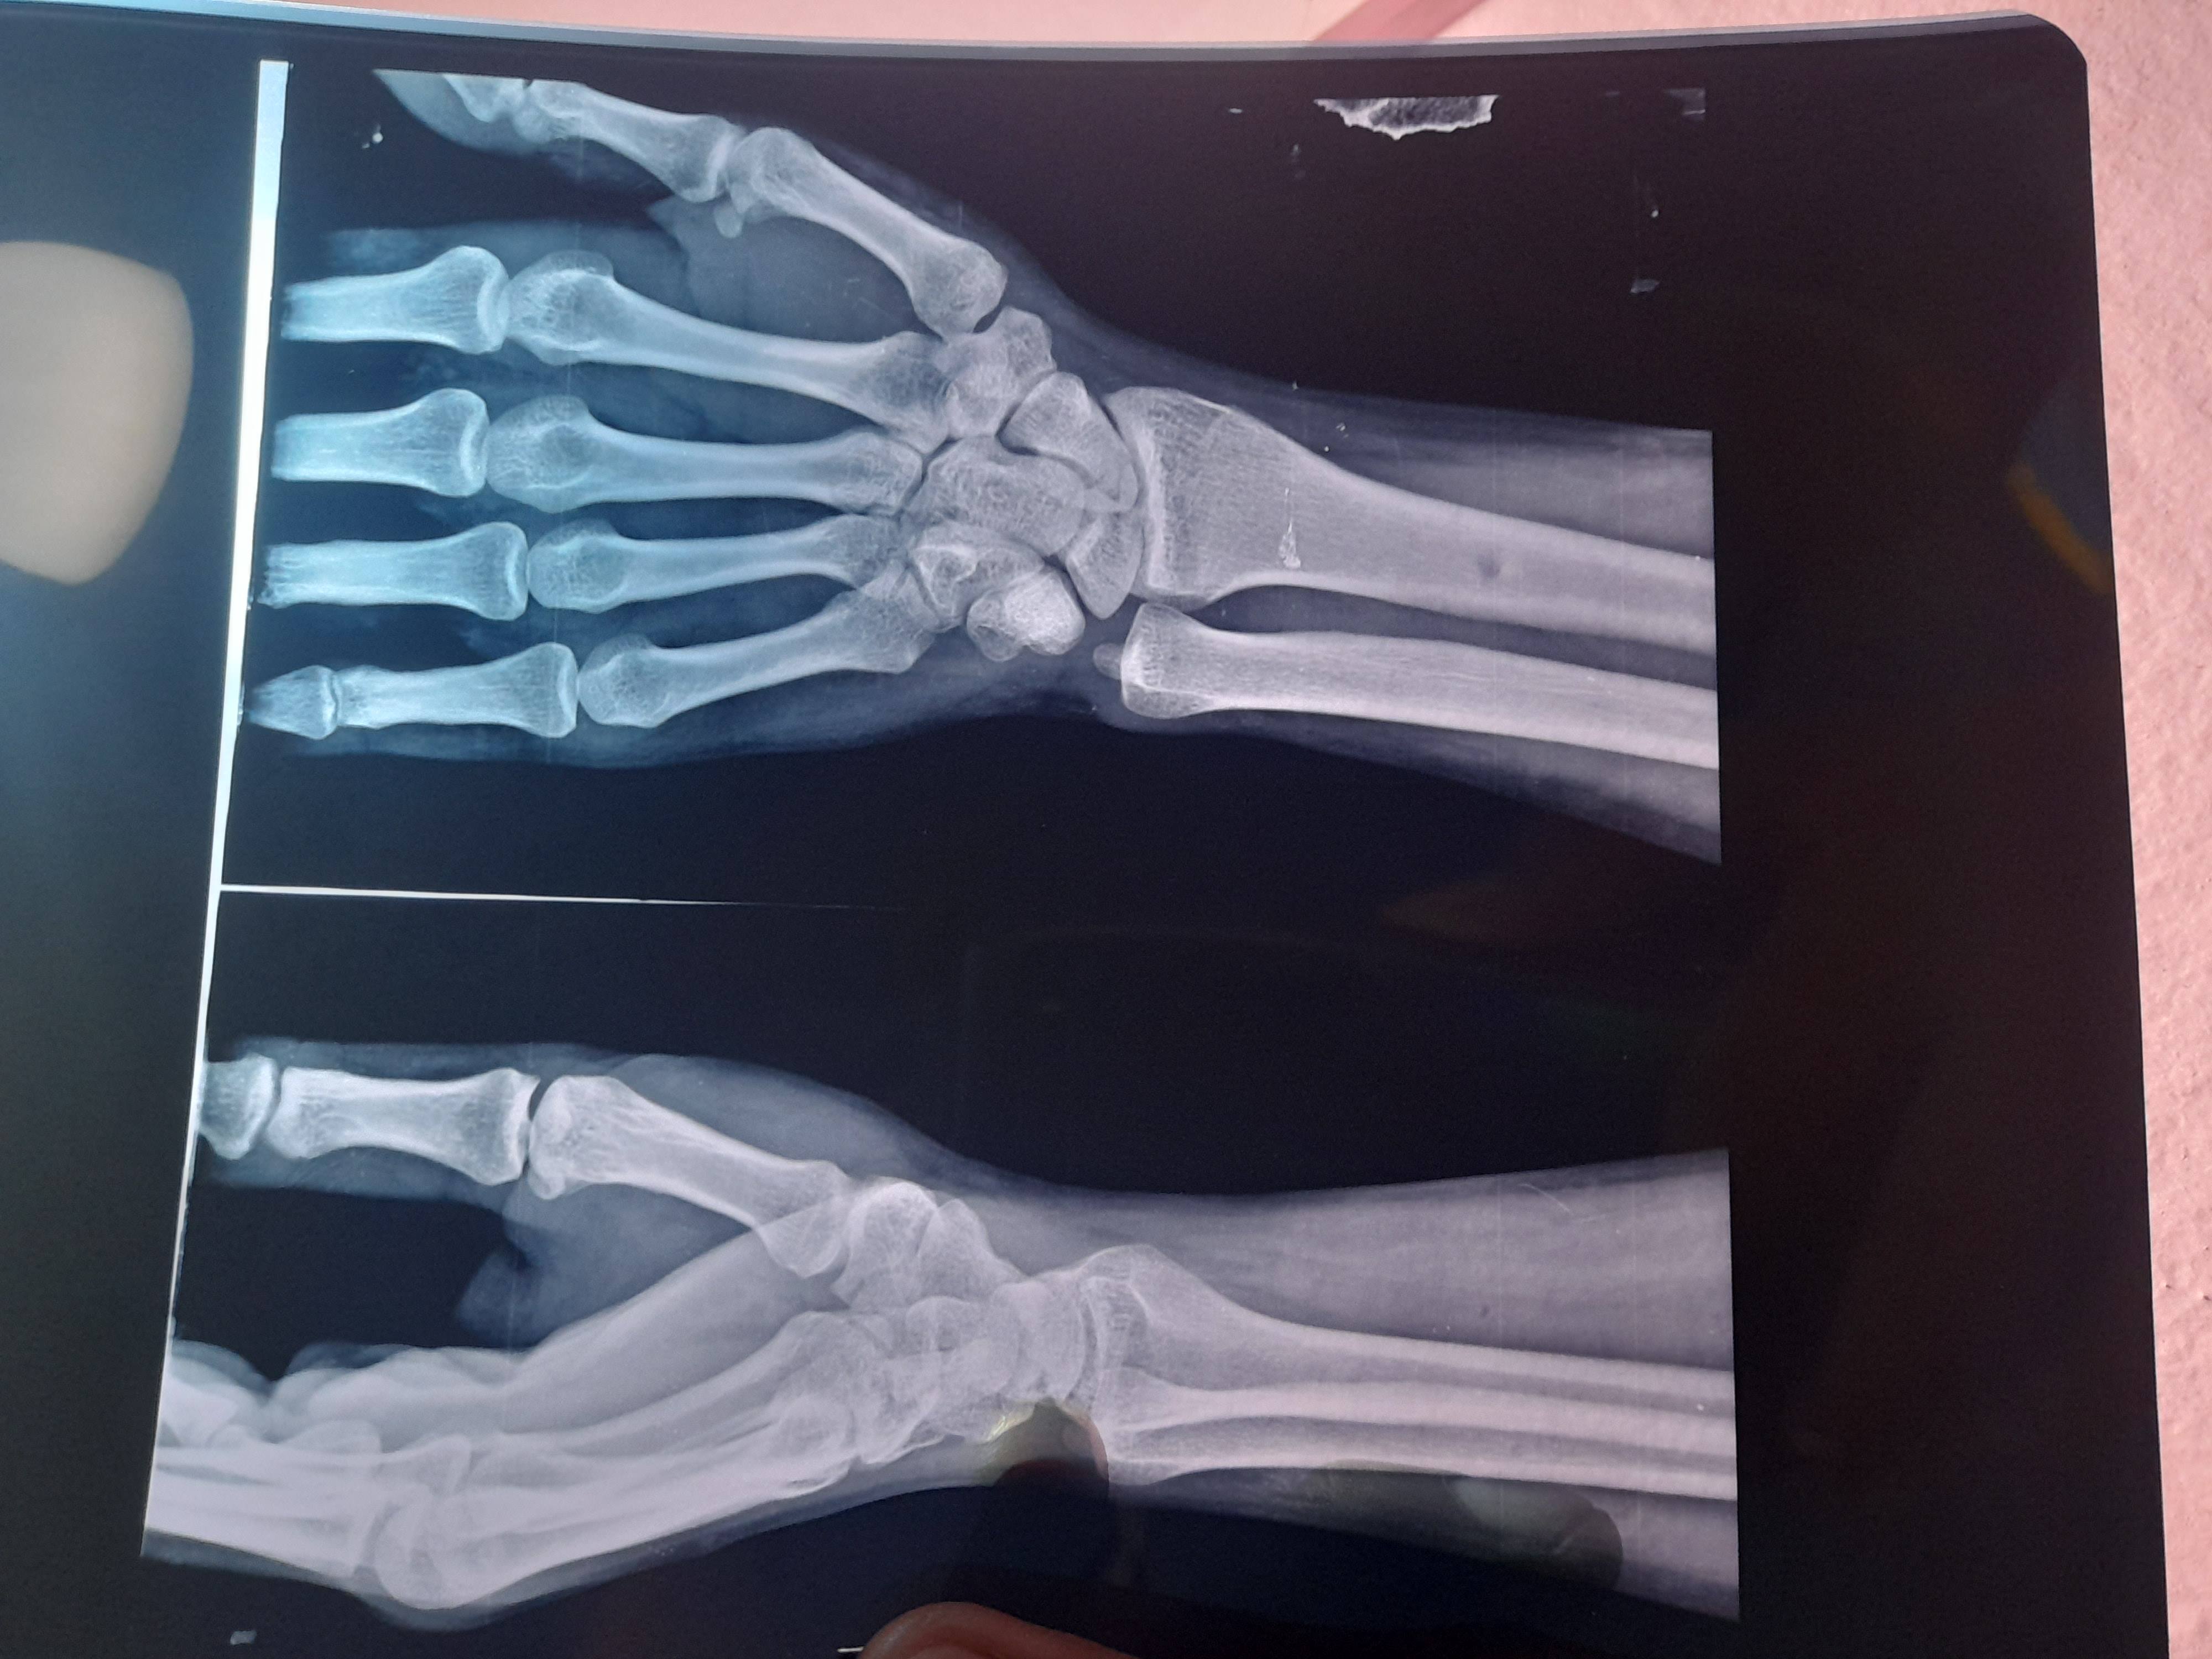

Wrist pain

Scaphoid bone pain

I have scaphoid fracture